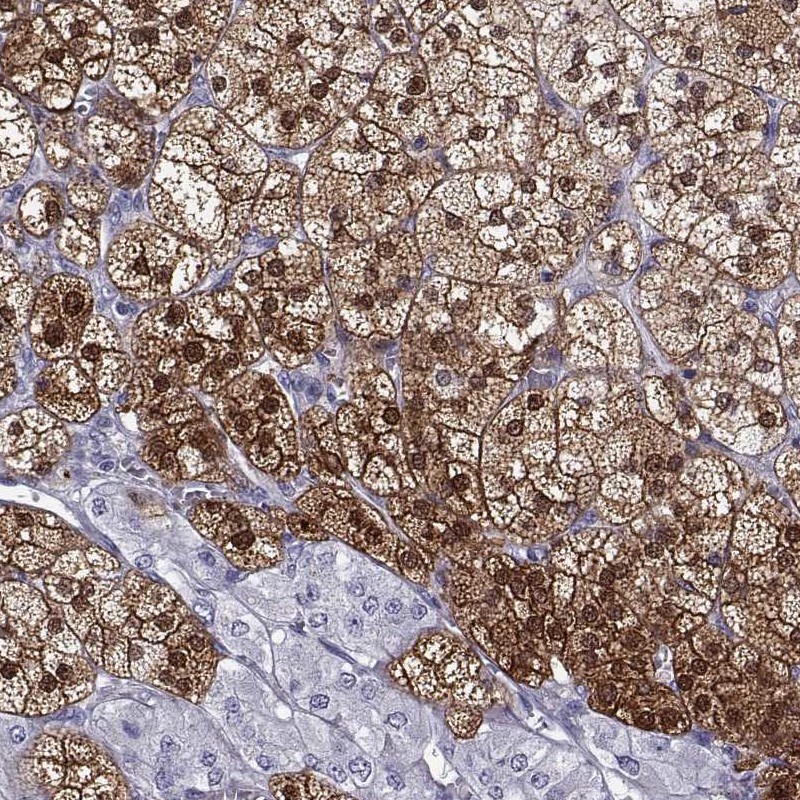

Immunohistochemistry analysis in human adrenal gland and cerebral cortex tissues using Anti-AKR1B1 antibody. Corresponding AKR1B1 RNA-seq data are presented for the same tissues.